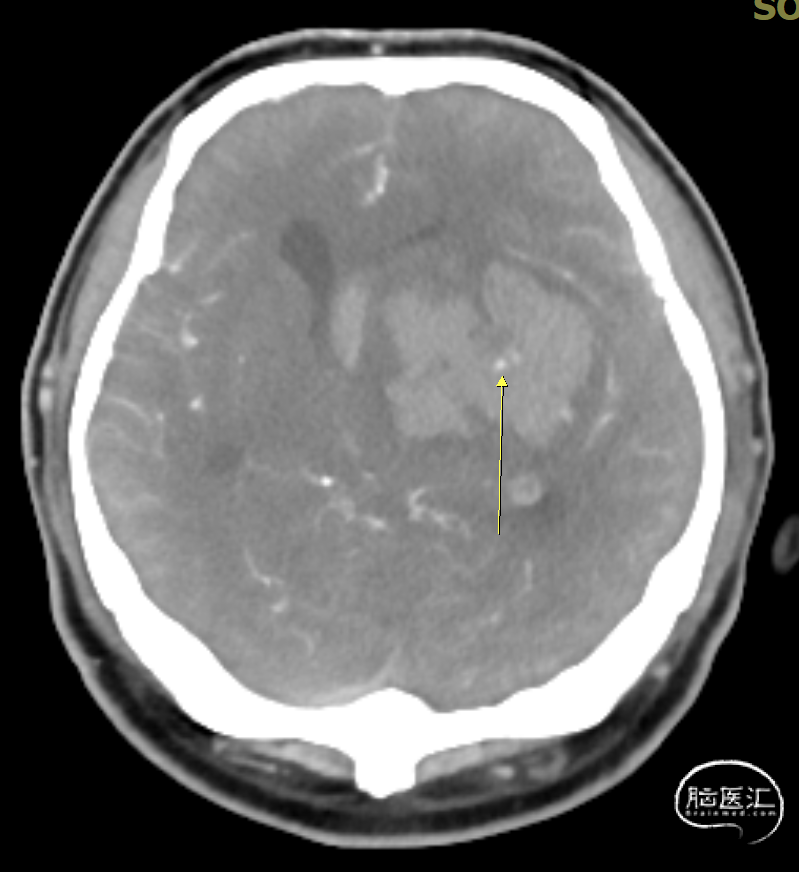

辅助检查:头胸部CT平扫2026-03-14我院脑出血并破入脑室,请结合临床复查,蛛网膜下腔出血。双肺少许纤维灶,双肺坠积性改变,请结合临床隔期复查,双肺少许小结节,考虑低危结节可能,建议结合临床年度随诊复查双肺部分小叶间隔增厚,肺水肿不除外,建议结合临床短期复查,冠脉壁钙化灶,胆囊结石。头颈部CTA2026-03-14我院颅内动脉轻度粥样硬化性改变,左侧优势型椎动脉,椎基底动脉迂曲延长。

CTA: